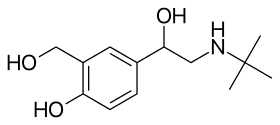

- Randomised control trials have shown that β2 agonists increase muscle strength, but do not modify disease progression. Follow-up time for most RCTs on β2 agonists is only around 12 months, hence results cannot be extrapolated beyond that time frame.